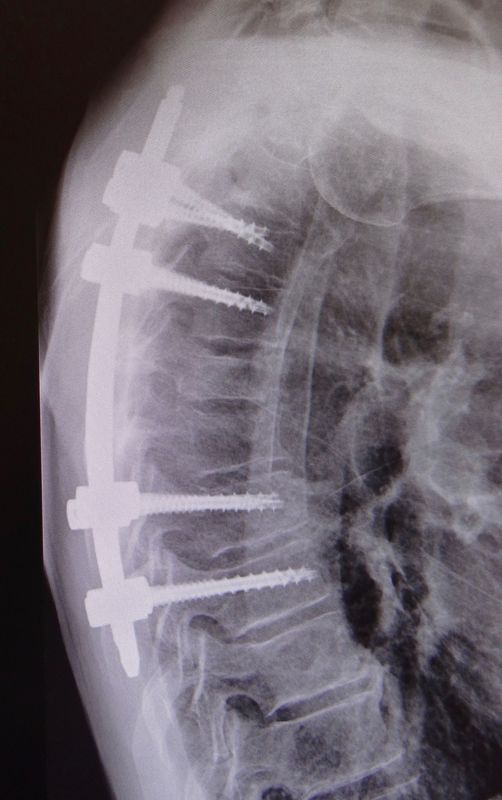

Des vis sont implantées dans deux ou plusieurs vertèbres afin de fixer l’instabilité. Une ou plusieurs cages sont également placées entre les vertèbres, une fois le disque intervertébral retiré pour permettre une fusion.

On distingue deux grands types de fracture vertébrale. La première catégorie se caractérise par les fractures traumatiques, qui surviennent lors d’un traumatisme majeur (accident de la voie publique, accident de sport, chute d’une hauteur > 2 mètres,…). La deuxième catégorie se définit par les fractures pathologiques. Ce sont des fractures qui surviennent spontanément ou lors de traumatisme mineur. Il existe toujours une cause sous-jacente à ce type de fracture comme l’ostéoporose, les tumeurs ou les métastases.

Le symptôme principal dans une fracture est la douleur (cervicale, dorsale ou lombaire) intense et survenant directement après le traumatisme. Dans le cas des fractures pathologiques, les douleurs peuvent survenir spontanément ou lors d’un traumatisme mineur. Lorsque la fracture déplace la vertèbre vers l’arrière, il arrive que les structures nerveuses (moelle épinière ou nerfs) soient comprimées, et des troubles dits neurologiques apparaissent, tels que l’engourdissement, les fourmillements, une faiblesse, voire même une paralysie.

Les fractures peuvent survenir n’importe où dans la colonne vertébrale, mais touche plus particulièrement les vertèbres dorsales et lombaires.

Le traitement va dépendre du type de fracture et de l’atteinte neurologique. Il va du traitement conservateur par corset ou minerve à la fixation par des vis avec parfois une résection de la vertèbre fracturée et le placement d’une cage en titane. Parfois, une injection de ciment (cyphoplastie) suffit à stabiliser la fracture.